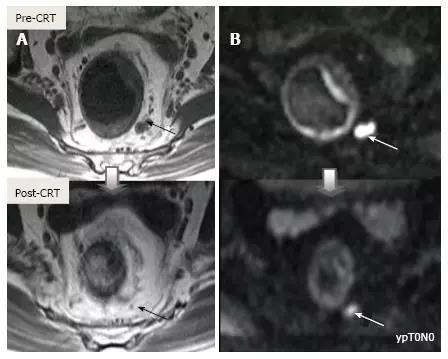

采用传统 MRI 序列对 CRT 后肿瘤重新分期的精确性差于初始分期,尤其在证实完全缓解(yT0),主要是很难将残留的肿瘤与纤维化、水肿和正常粘膜区分开,因此 CRT 后正常的 2 层直肠壁提示为完全缓解,而残留纤维化既可以是肿瘤残留也可以是完全缓解(图 17)。

实际上 CRT 后 T2 加权 MRI 后上纤维化的信号强度很低,而残留肿瘤区域则为中等强度,仔细评估高分辨图像和 DWI 是能区分小的残留病变和纤维化的(图 18)。

图 17. 新辅助放化疗后肿瘤重新分期。在不同患者的 T2 加权 MR 图像上分别显示(上:治疗前,下:治疗后)。A. 在 ypT0 直肠肿瘤中,治疗后的轴位图像显示正常的两层直肠壁(箭头),对应完全缓解;B. 在 ypT3 直肠肿瘤中,治疗后的轴位图像显示正常的双层直肠壁(箭头)。这是 MR 评估完全缓解的假阴性例子;C. 在 ypT0 直肠肿瘤中,原有肿瘤区域治疗后呈现厚的、纤维化的低信号强度疤痕(箭头)。